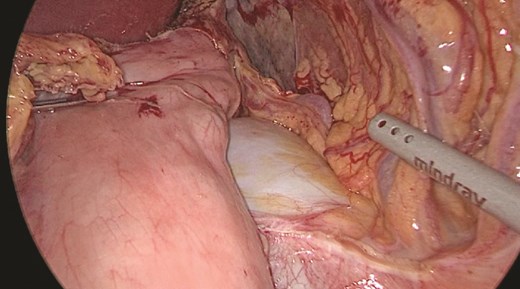

Multidisciplinary discussion was held to evaluate the most appropriate course of action for the patent condition, and the consensus was reached to pursue embolization as a first intervention. Embolization was performed by interventional radiology with no complications post-procedure, and the patient was optimized prior to her procedure. Patient was taken to the operating room in stable conditions. The spleen was enlarged around 20 cm. Inferiorly, the omentum and part of the transverse colon was attached to the spleen (Fig. 3), so we freed the omentum from the splenic tissue. The dissection continued until reaching short gastric vessels and entering the lesser sac (Fig. 4). Once the lesser sac was entered, the splenic vessels were identified (Figs 5 and 6), the splenic vein was hugely dilated with multiple collateral branching vessels at the hilum. Gaining posterior mobilization of the vein was challenging. The splenic artery was tortuous from the insertion around itself (Fig. 7). After complete mobilization of the fundus, we elected to divide each vessel starting with the splenic artery so we can achieve full mobilization of the vein (Fig. 9). After controlling the splenic artery, the splenic vein was dissected proximal to the splenic hilum (Fig. 8). It was hugely dilated and its wall is thickened secondary to AV fistula. It was difficult to achieve circumferential dissection, so we decided at that moment to convert to laparotomy to complete ligating the vein and to retrieve the specimen (Fig. 10a and b).

Splenic vein mobilized from the side. Clips seen on branches of the vein.